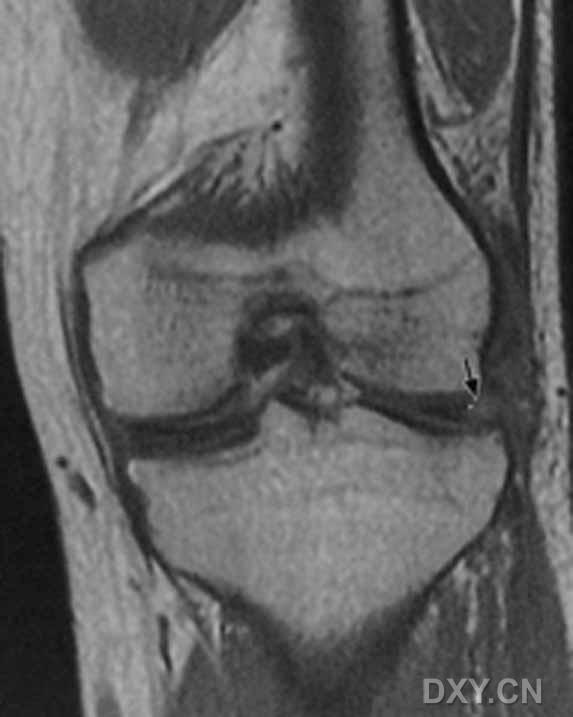

| 双前、后交叉韧带征